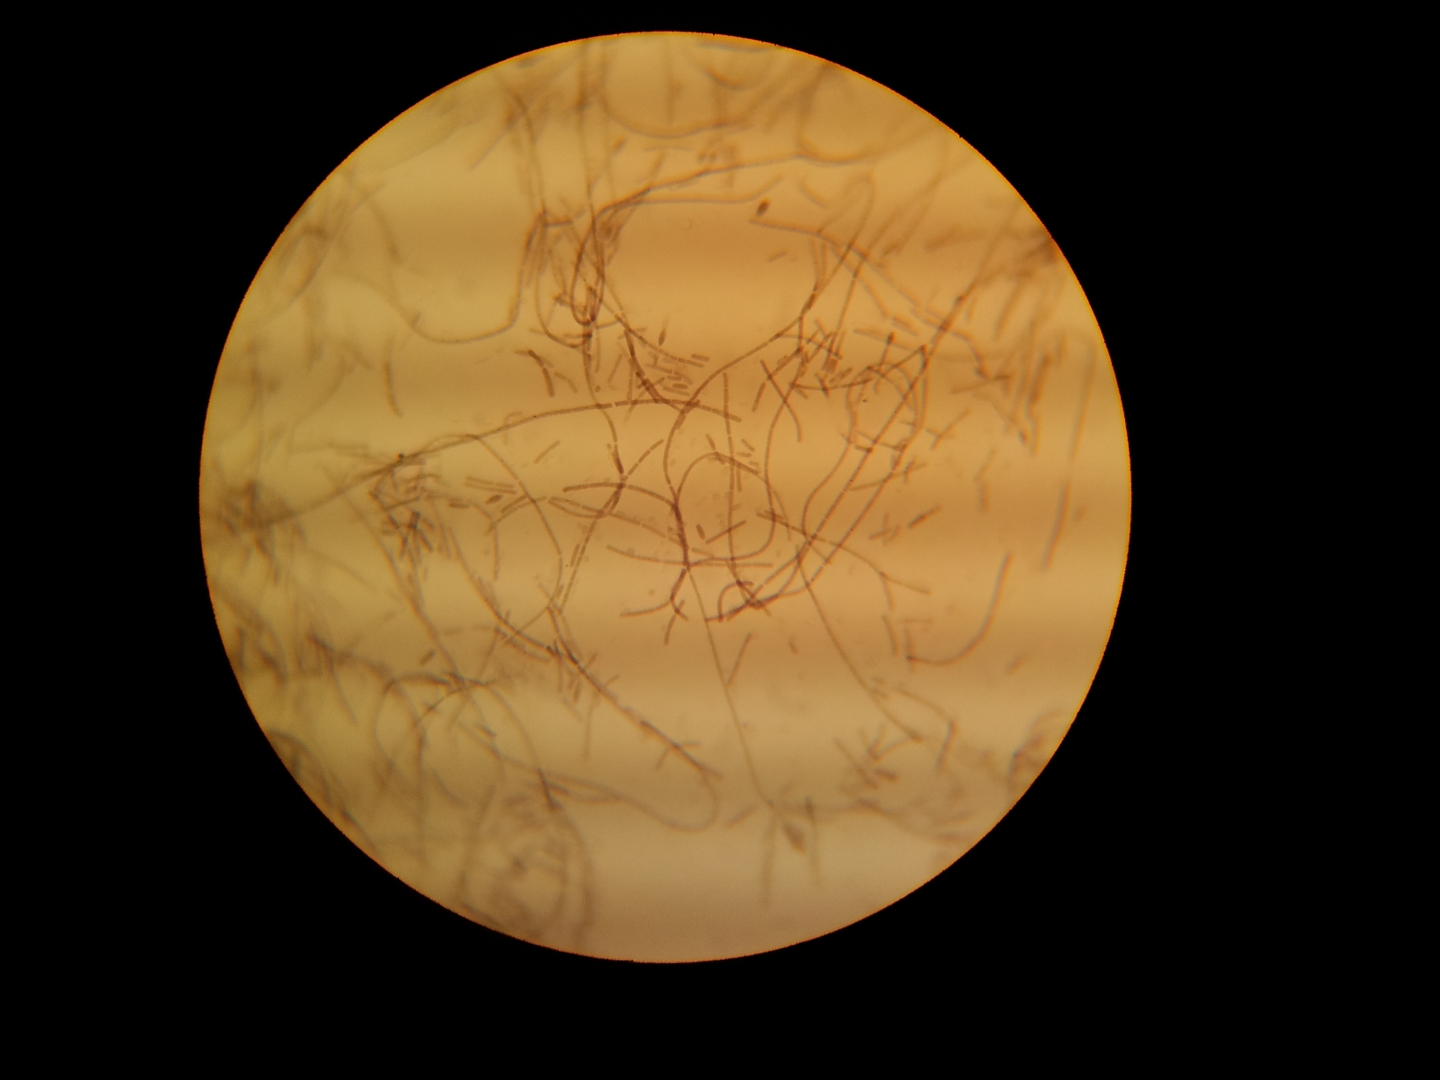

Споры сибирской язвы под микроскопом . Статья на конкурс «Био/Мол/Текст»: Сибирская язва — смертельно опасное инфекционное заболевание, известное с древности и успевшее оставить свой кровавый след на страницах истории .

Сибирская язва известна с древних времен . Возбудитель заболевания впервые выделен Р . Кохом в 1876 году . Рис . 16 . На фото возбудители сибирской язвы . Слева вид под микроскопом . Справа — культура возбудителя .

Сибирская язва . — это особо опасная инфекционная болезнь, поражающая кожный покров затем из лопнувшего пузырька образуется язва с приподнятыми над уровнем кожи краями В лаборатории сначала бактерии изучают под микроскопом, затем на специальной среде . . .